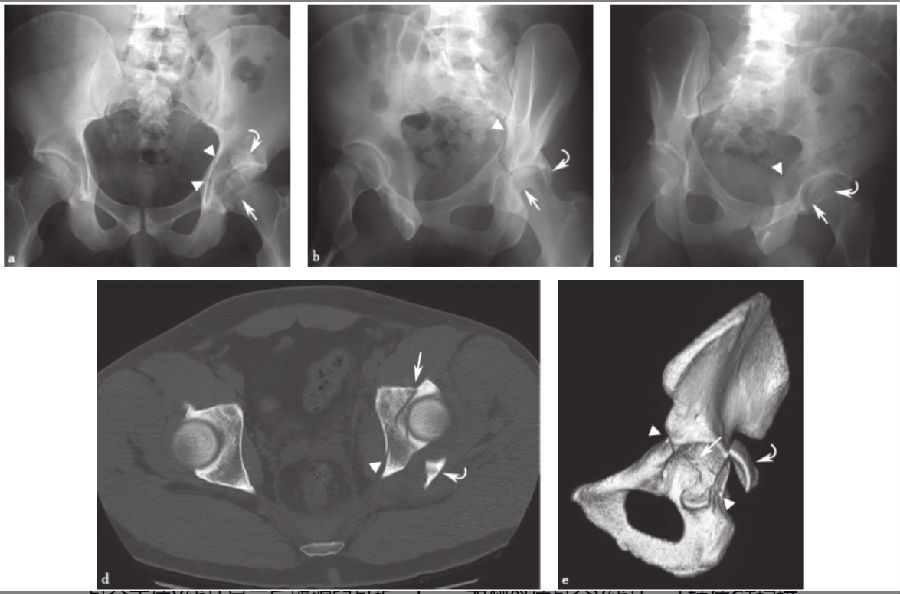

3、横行髋臼骨折:

髋臼的横行骨折(图12)仅限于髋臼,而不涉及闭孔环。横行髋臼骨折必须涉及髋臼的前部和后部,因此髂耻线和髂坐线在X线片上显示不连续。该骨折线从髋臼向上和向内延伸。在CT上,当从下向上滚动时,在后续的CT图像上可以看到特征性的矢状面骨折线向内侧移动。尽管在解剖学上不是横行的,但断裂平面相对于髋臼是横行的,其在下部和前部相对倾斜。在髋臼面的CT重建图像上可以最清楚地看到这种骨折面走向。

图12 横行髋臼骨折a.骨盆正位X线片;b、c.双侧斜位骨盆X线片;d.轴向CT扫描;e.右侧髋臼三维CT重建侧面观显示骨折走向(直线箭头)横向于髋臼,破坏髂耻线和髂坐线(箭头)。注意CT扫描时特征性的矢状-斜向骨折平面(d)。箭头示破坏的髂耻线和髂坐线,直线箭头示横向于髋臼的骨折线。

4、横行后壁骨折:

横行后壁骨折(图13)是一种前面描述的横行骨折,伴随着粉碎性的后壁骨折,这种骨折通常会被置换。与孤立的横行骨折一样,关键在于判断闭孔环是否被破坏,若闭孔环完整,则不考虑双柱和T形骨折。如同简单的横行骨折一样,这种骨折类型不会延伸到髂骨翼。

图13 横行后壁骨折a.骨盆正位X线片显示后壁髋臼骨折;b、c.双侧斜位骨盆X线片;d.轴位CT扫描;e.髋臼侧面三维CT扫描,右半骨盆和股骨去除后,显示横向骨折(直线箭头)破坏髂耻骨和髂坐线(箭头),伴有移位和粉碎的后壁骨折片段(弯曲的箭头)。

在X线片上,髂耻线和髂坐线的破坏与孤立的横行骨折一样。然而,与孤立的横行骨折不同,可以看到额外的后壁粉碎。在没有移位的情况下,由于碎片重叠在股骨头上,所以在前后位X线片上很难识别后壁的粉碎。倾斜Judet位X线片和CT有助于显示粉碎的后壁组件。